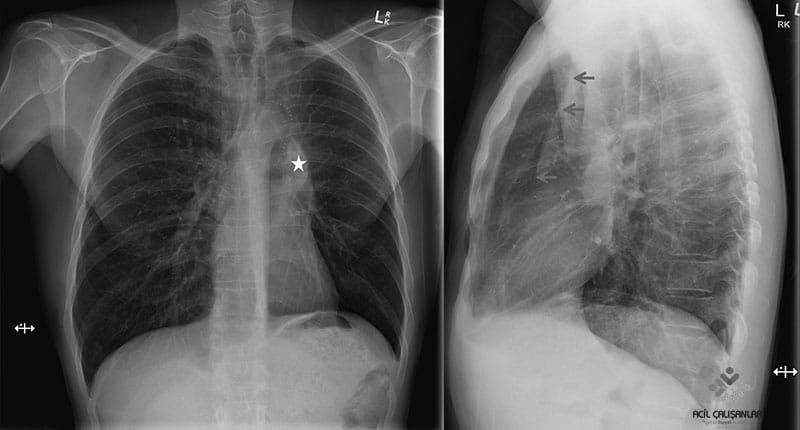

Kalp-Mediasten: Kardiotorasik oran değerlendirilmeli ve erişkinler için 1:2 sınırının altında olup olmadığı, kalbin konfigürasyonu ve olası büyüklük farkları değerlendirilmelidir. Kalp kontrol edildikten sonra aorta ve pulmoner arterlerin kalibrasyonları değerlendirilir.

Mediastinal Kayma (shift): Mediastinal organların yer değiştirmesini ifade eder

Trakea ve kalbin pozisyonuna bakmak gerekir

Hiluslar

Hiluslar başlıca pulmoner artreler, kısmen süperiyor pulmoner venlerden kaynaklanır. Her iki hilus genişliği kitle ve lenfadenopati gelişimlerinin değerlendirilmesi için önemlidir. Sol hilus yaklaşık olarak sağ hilustan 25 mm daha yukarda yer alır, eşit seviyede olabilir. Hilusların dansitesi aynı olmalıdır ve dış konturu konkav veya düz olmalıdır. Bu yapılar ile birlikte mediasten konturlarının değerlendirilmesi ile olası kitleye bağlı genişlemeler kontrol edilmiş olur.